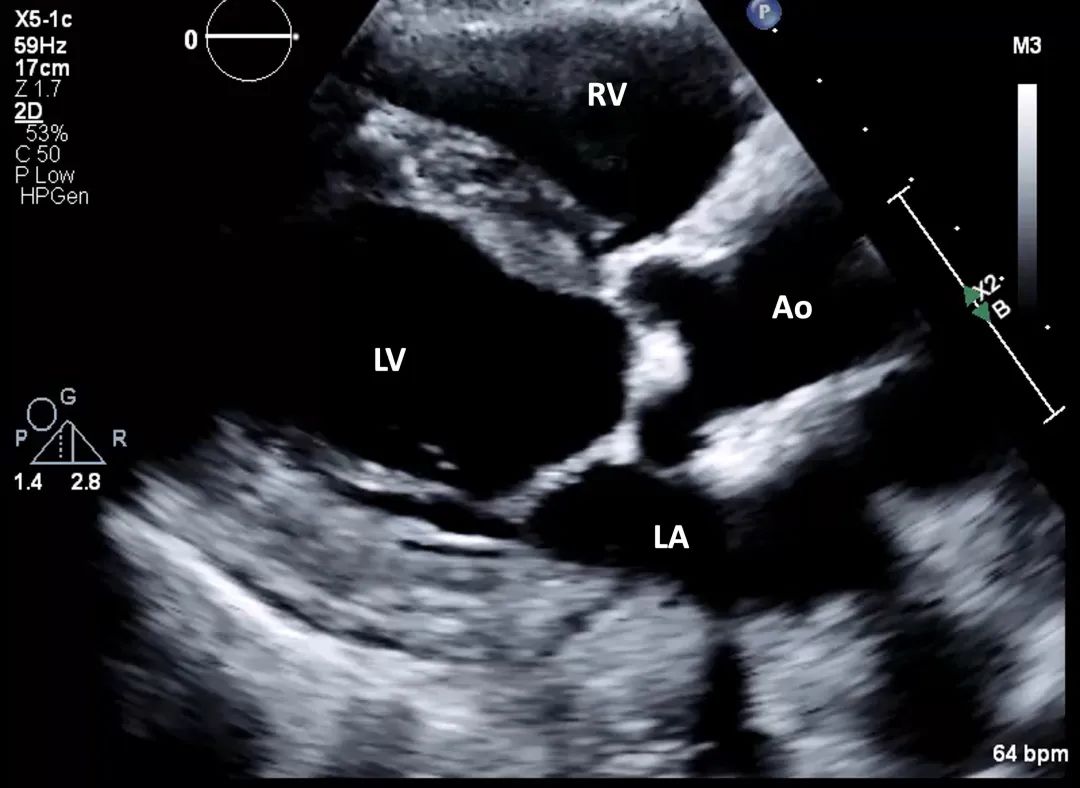

1、使用经胸超声心动图探头,从胸骨旁长轴切面开始操作流程,以评估左室射血分数、左室壁厚度,以及主动脉瓣和二尖瓣(图2,视频1)。

图2. 胸骨旁长轴切面

使用经胸超声心动图探头,从胸骨旁长轴切面开始,评估左室射血分数和室壁厚度。Ao = 主动脉(aorta);LA = 左房(left atrium);LV = 左室(left ventricular);RV = 右室(right ventricular)。

视频1. 左室胸骨旁长轴切面